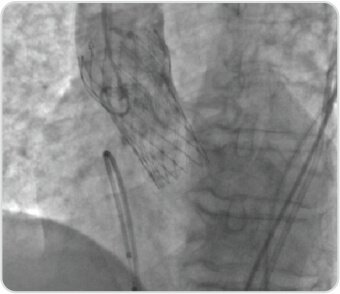

Trans Catheter Aortic Valve Implantation (TAVI) – Case-3

Case-3

80 year old lady presented with a history of high grade fever of 2 weeks duration and exertional syncope to us. PET-CT revealed miliary tuberculosis and severe calcific aortic stenosis. The patient was treated successfully with self-expanding 23 mm Evolute -R under conscious sedation and was discharged in a stable condition.